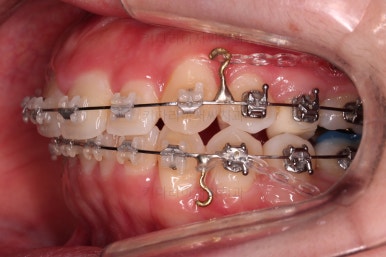

미니스크류가 구성되었고요.

기울기와 돌출입을 개선하고자 이러저리 밀고당고 하는 모습입니다.

오히려 이전 사진보다 치열이 더 틀어지고 잘 안맞는 모습이죠?

환자분도 이때부터는 매우 힘들어하시긴 합니다.

괜히 잘 맞아보이는 걸 손대서 이상해지는 느낌일거거든요.

잘 설명 드려가면서 좀 더 좀 더 진행해 봅니다.